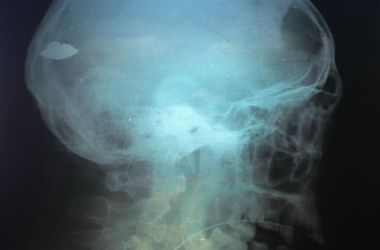

"Спасли 39-летнего Александра из Черновцов. Ранение в Песках, осколки в голове. Много суток в реанимации. Завтра последняя пластика дефекта черепа. Андрей Сирко (нейрохирург – ред), похлопывая солдата по плечу, сказал – величайшее испытание ты уже прошел, титановый ты не один", – пишет медик.